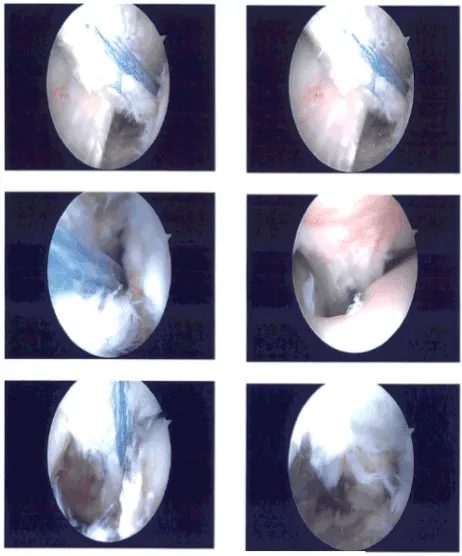

The ACI Fiber Links were also tightened after cycling the knee and knotted to each other. The sutures were cut with the use of blades. Final pictures were taken and saved. The knee was thoroughly irrigated and ranged.

Clinical photo

After discussing treatment options, we have decided to proceed with formal physical therapy as well as a home exercise program for rehabilitation of the knee. We went over the arthroscopic pictures and removed the stitches during the visits.